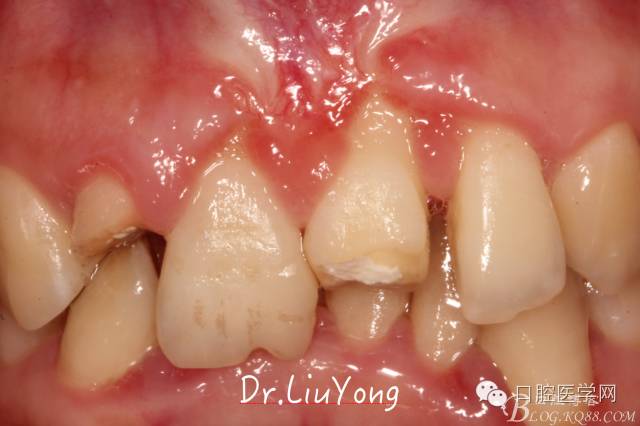

檢查:面部對稱無腫脹畸形,張口度正常,口內(nèi)檢查可見A2牙冠缺失,可見直徑約1.5mm左右穿髓孔,冷熱刺激痛+,叩痛+,探痛+,近中斷面探診位于齦下1.5mm,A1B1B2松動2-3度,B1牙冠缺失1/2,冷熱刺激痛-,叩痛+,B2牙冠完整,A2-B2牙齦紅腫,探診極易出血,全口口腔衛(wèi)生差,牙結(jié)石++,A1B1之間牙齦乳頭紅腫嚴(yán)重,B1唇側(cè)牙齦萎縮明顯,牙齦邊緣可見縫線兩處,局部有滲出,齦緣冠方1mm處見白色骨塊,松動,觸痛明顯,觸及骨塊時可見B1及B2近中唇側(cè)牙齦動度,B1B2之間唇側(cè)牙齦乳頭缺失,B2近中根面可見大量牙結(jié)石。重度深覆合,牙尖交錯位時C3-D2咬至上前牙腭側(cè)齦緣,A1切端咬至C12唇側(cè)齦緣。其余牙齒未見明顯異常。

術(shù)前口內(nèi)照片如下: